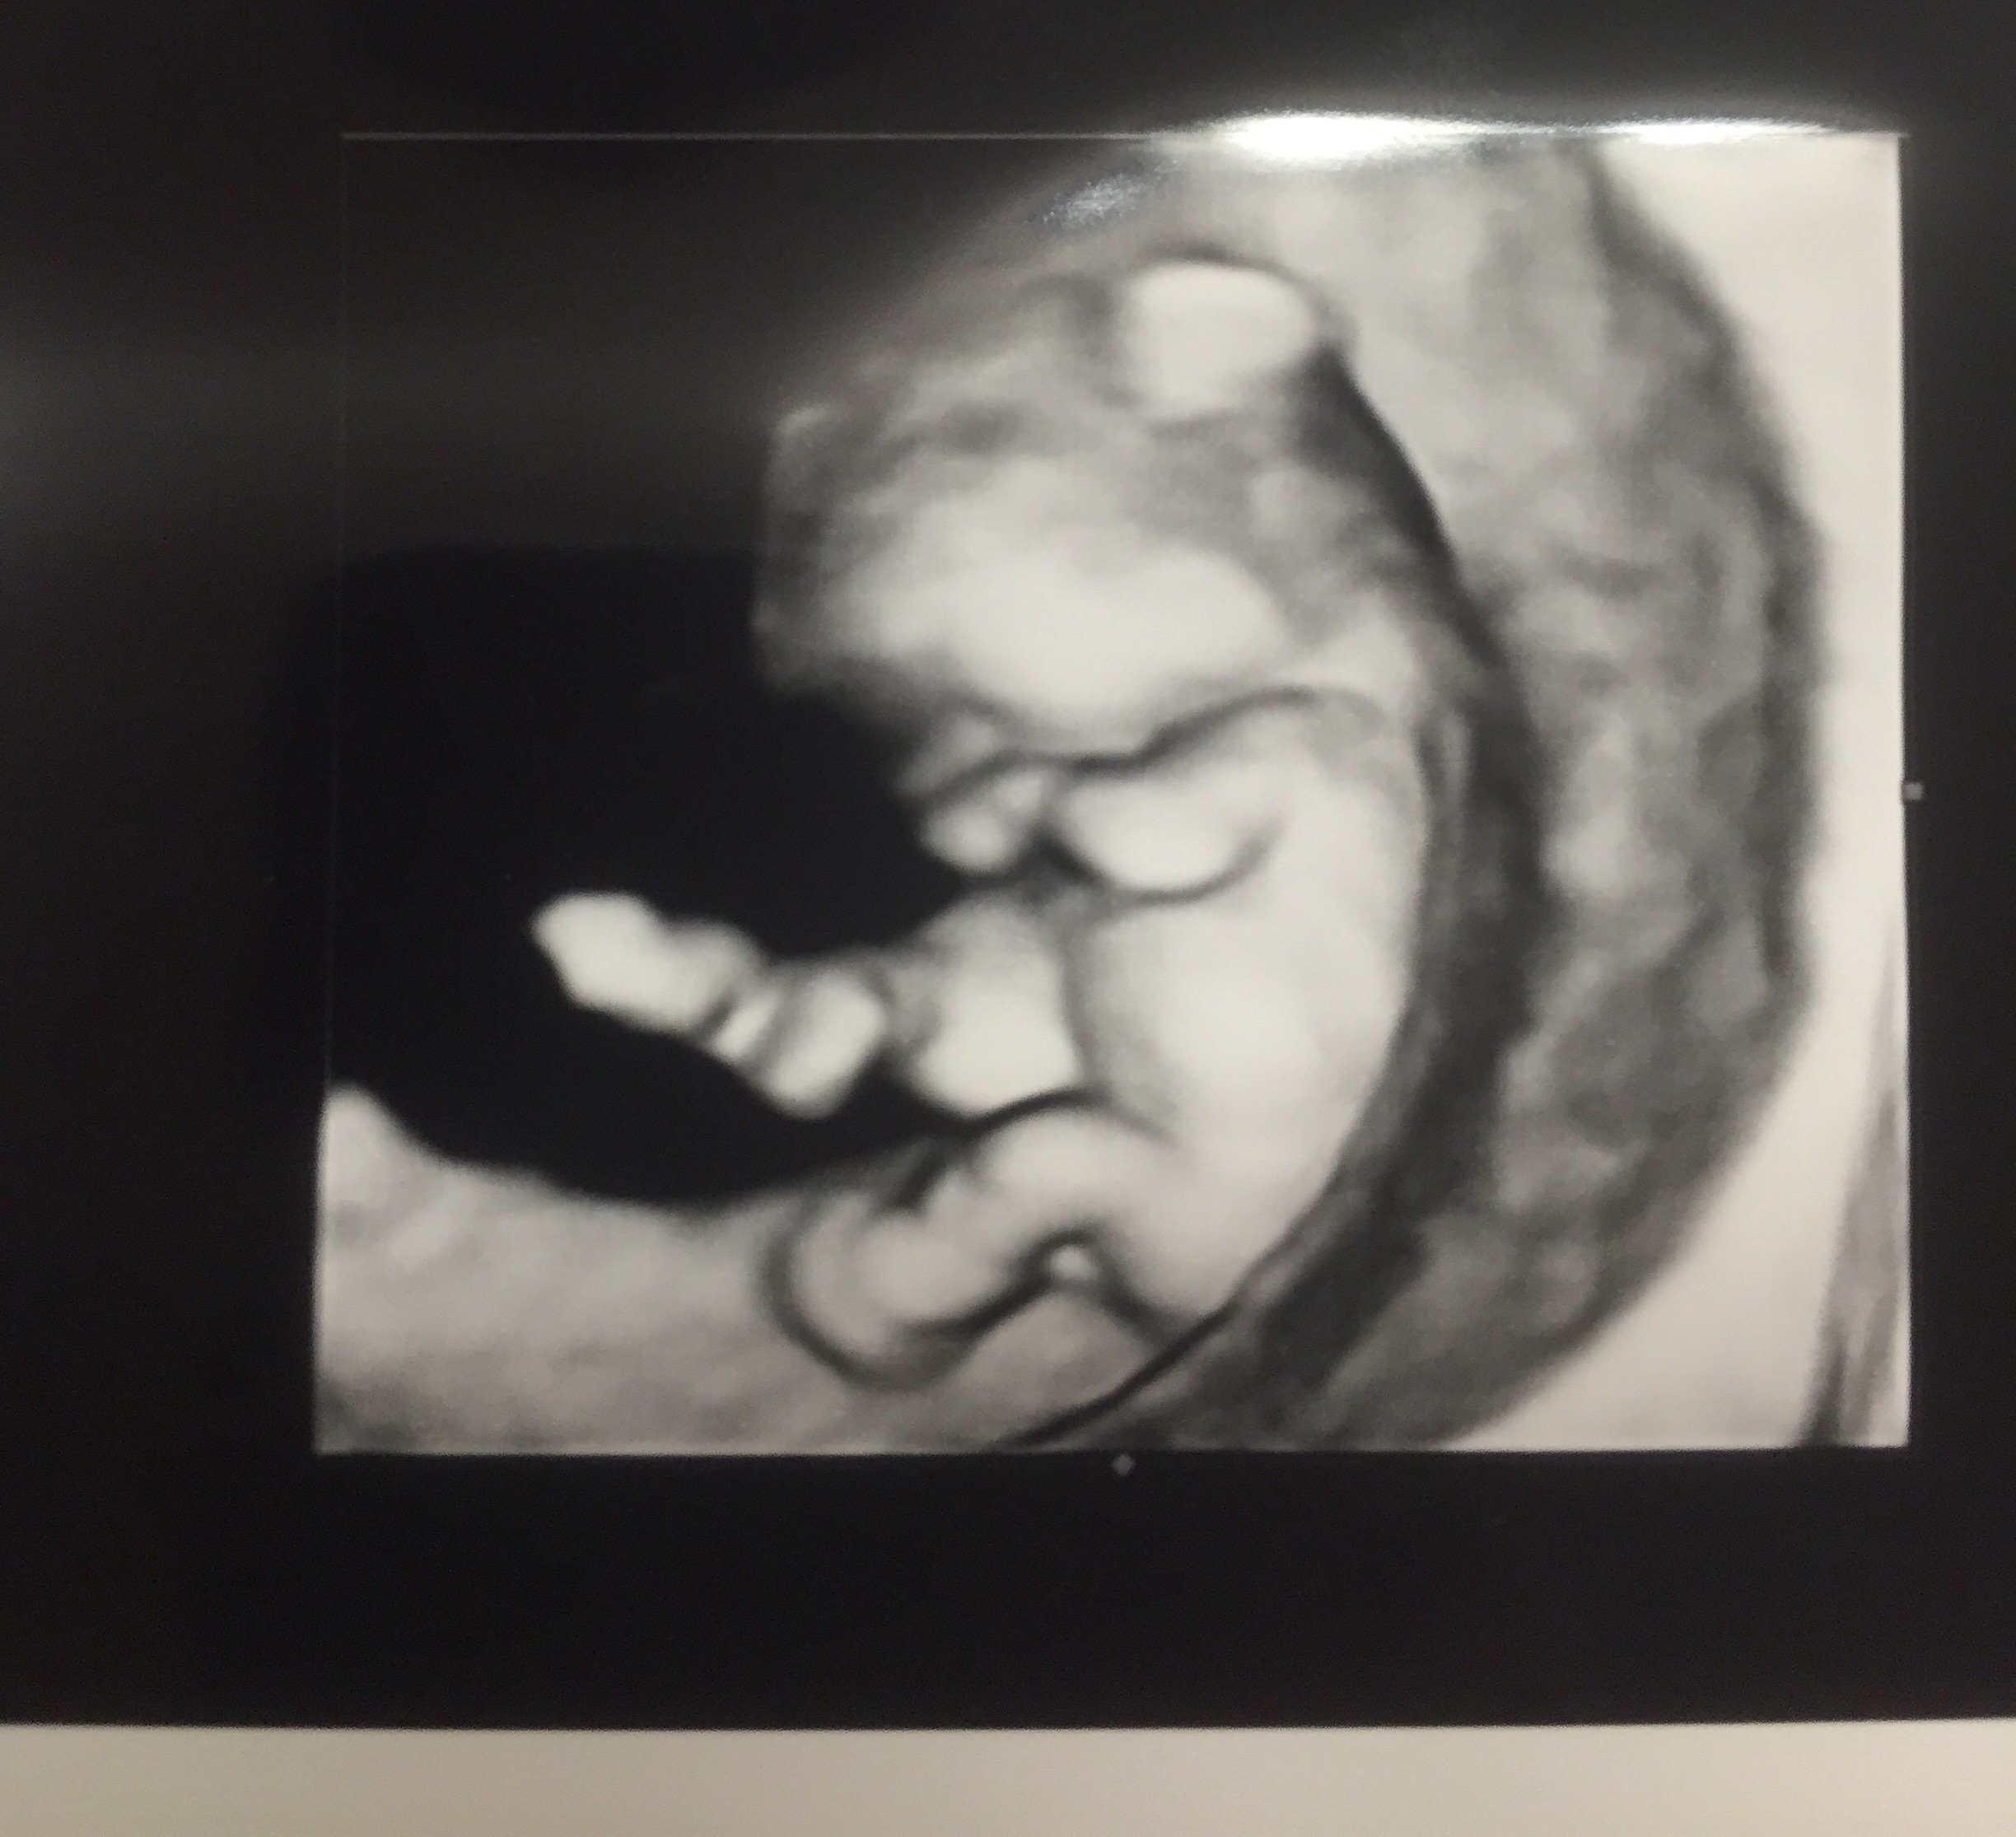

@sincerelymom I can't believe how well detailed you can see your little one in the first picture! I go Friday for my us and can not wait!

Yes, I was shocked myself! I think because they did a transvaginal they were able to do a 3-D pic. They actually gave me a few 3-D pics, but I picked my favorite for the post! Also- I am 10 1/2 weeks so baby is pretty big compared to a 6- or even 8-week u/s.